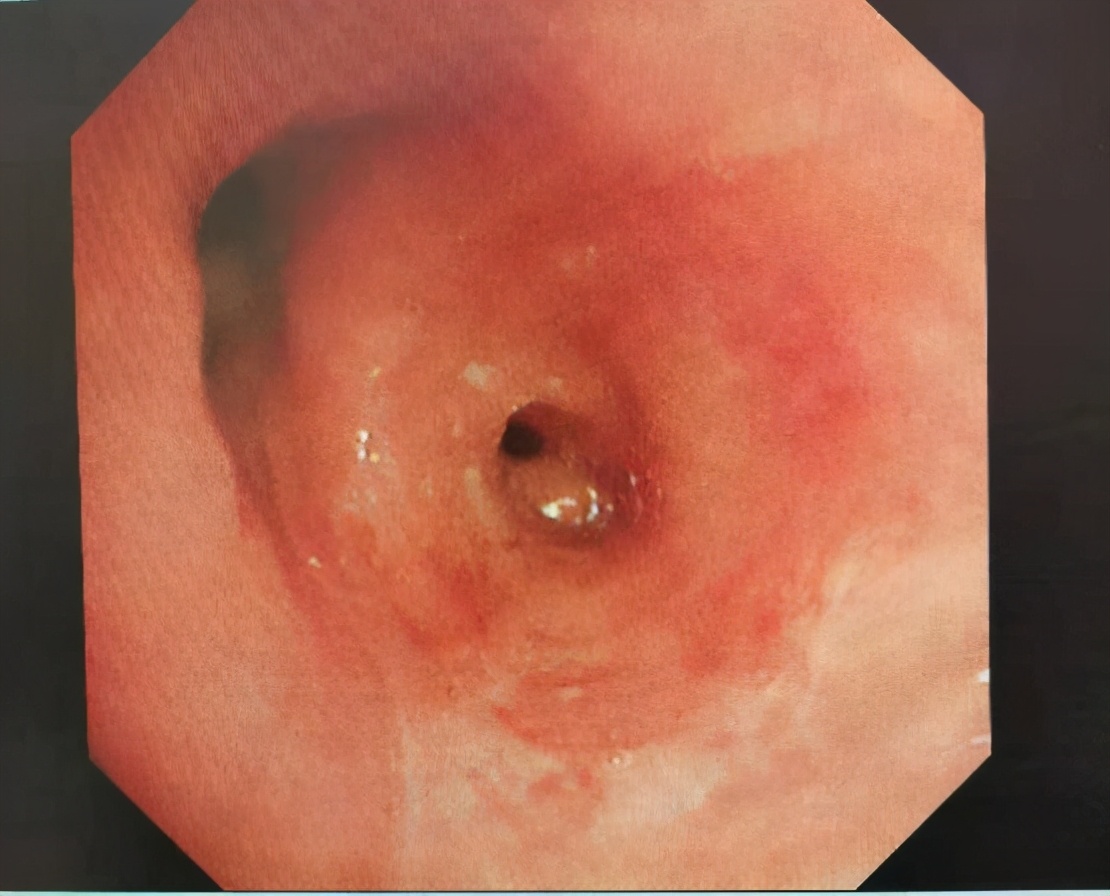

入院给予积极胸腔穿刺引流后,安福成主任给予患者行支气管镜检查可见左舌叶支气管开口处巨大腔内肿物,阻塞左舌叶约95%,这正是造成患者呼吸困难的主要原因。

经过支气管镜活检,病理诊断为真菌感染,之后给予两次支气管镜下两性霉素B药物滴入治疗,并给予全身抗真菌治疗,咳嗽、咳痰、胸闷症状有所改善,考虑支气管内肉芽肿阻塞远端气道导致病情的反复发生,与患者家属充分沟通后,予精心准备,在麻醉医生的配合下,完成了经支气管镜二氧化碳冻融,经多次镜下治疗,患者左舌叶气道基本通畅。